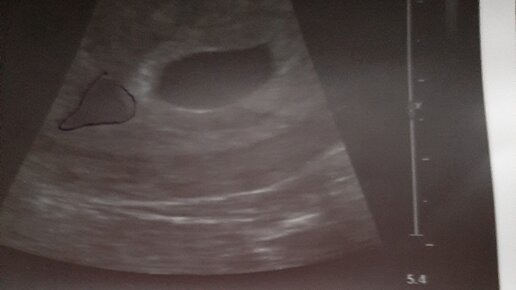

Деформировано плодное яйцо на УЗИ — это приговор? Рассказывает ваш репродуктолог Кряжева Елена Андреевна

Ультразвуковая диагностика в акушерстве. Неразвивающаяся беременность

ВАЖНЫЕ ПАРАМЕТРЫ ПЛОДНОГО ЯЙЦА ДЛЯ НОРМАЛЬНОГО РАЗВИТИ БЕРЕМЕННОСТИ | Как выглядит плодное яйцо